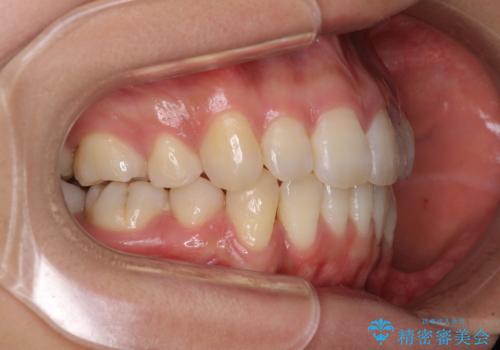

- 以前の矯正治療の後戻りにより、上下の前歯がでこぼこになってしまったことを気にして来院された患者様です。

口元がこれ以上突出することなく前歯の叢生が改善できるよう、歯と歯の間を削ってスペースを獲得し、インビザラインを用いて整えていくこととしました。

目安の装着時間である1日22時間をしっかりと実践してくださり、半年強という短期間で治療を終えることができました。